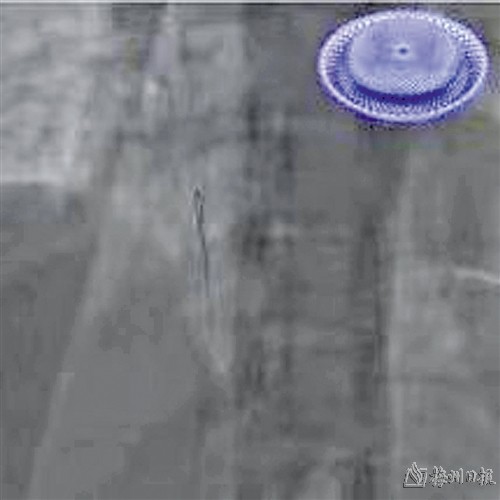

PFO封堵示意图

生物可降解PFO封堵器

常规金属PFO封堵器可见显影

生物可降解PFO封堵器无显影

详细讨论患者病情后,专家团队决定为患者实施经导管可降解卵圆孔未闭(PFO)封堵术。手术在DSA及超声引导下开展,手术团队娴熟地为患者建立了手术通路后,将国产可降解封堵器精准送达患者卵圆孔未闭处,依次展开、锁定、释放,封堵器像两把撑开的小伞,牢牢夹合房间隔,完成封堵,手术成功!